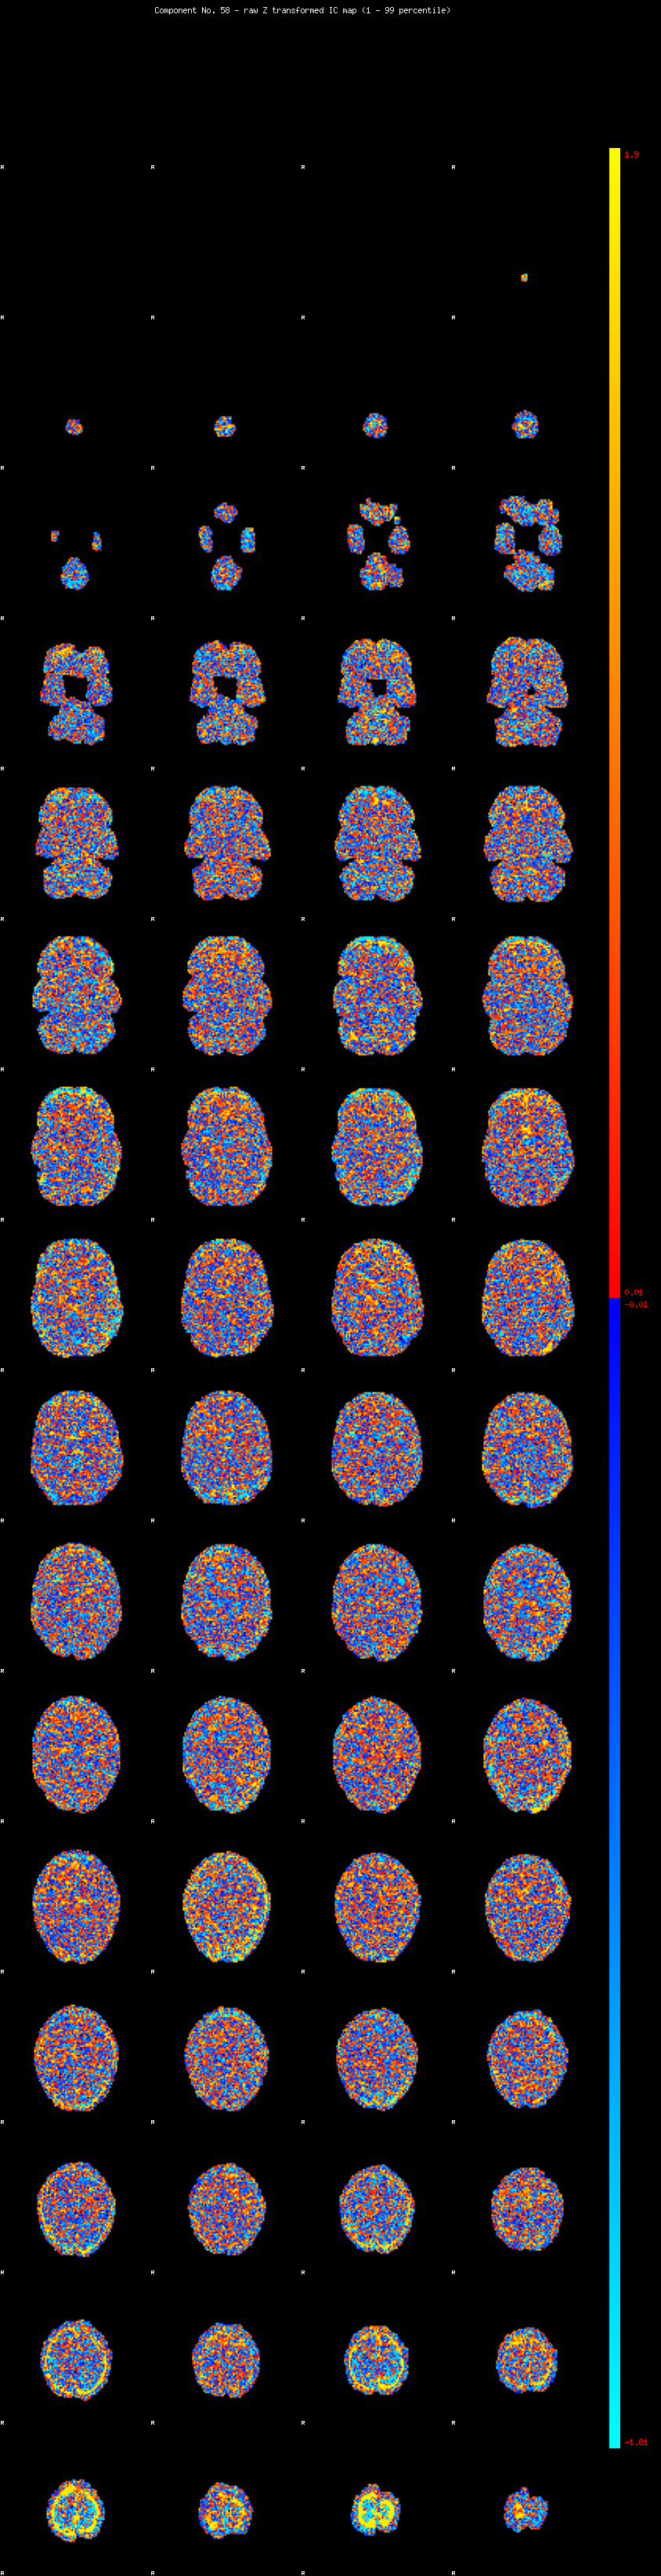

IC_58 Mixture Model fit

Means : 0.000000 2.705990 -2.751573

Vars : 1.000000 2.878072 0.715754

Prop. : 0.970949 0.020324 0.008726